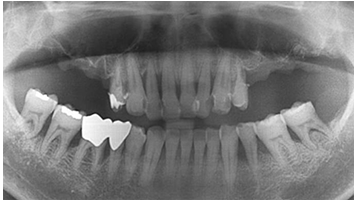

W Dental Clinic Before & After

치료 전후사진

Before

After

뼈이식